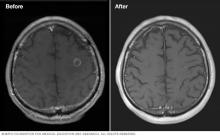

Brain tumor before and after treatment

Brain tumor before and after Gamma Knife treatment

Malignant brain tumor before (left) and 111 months after Gamma Knife stereotactic radiosurgery (right)

• Malignant tumors. Cancerous (malignant) tumors may shrink more rapidly, often within a few months.